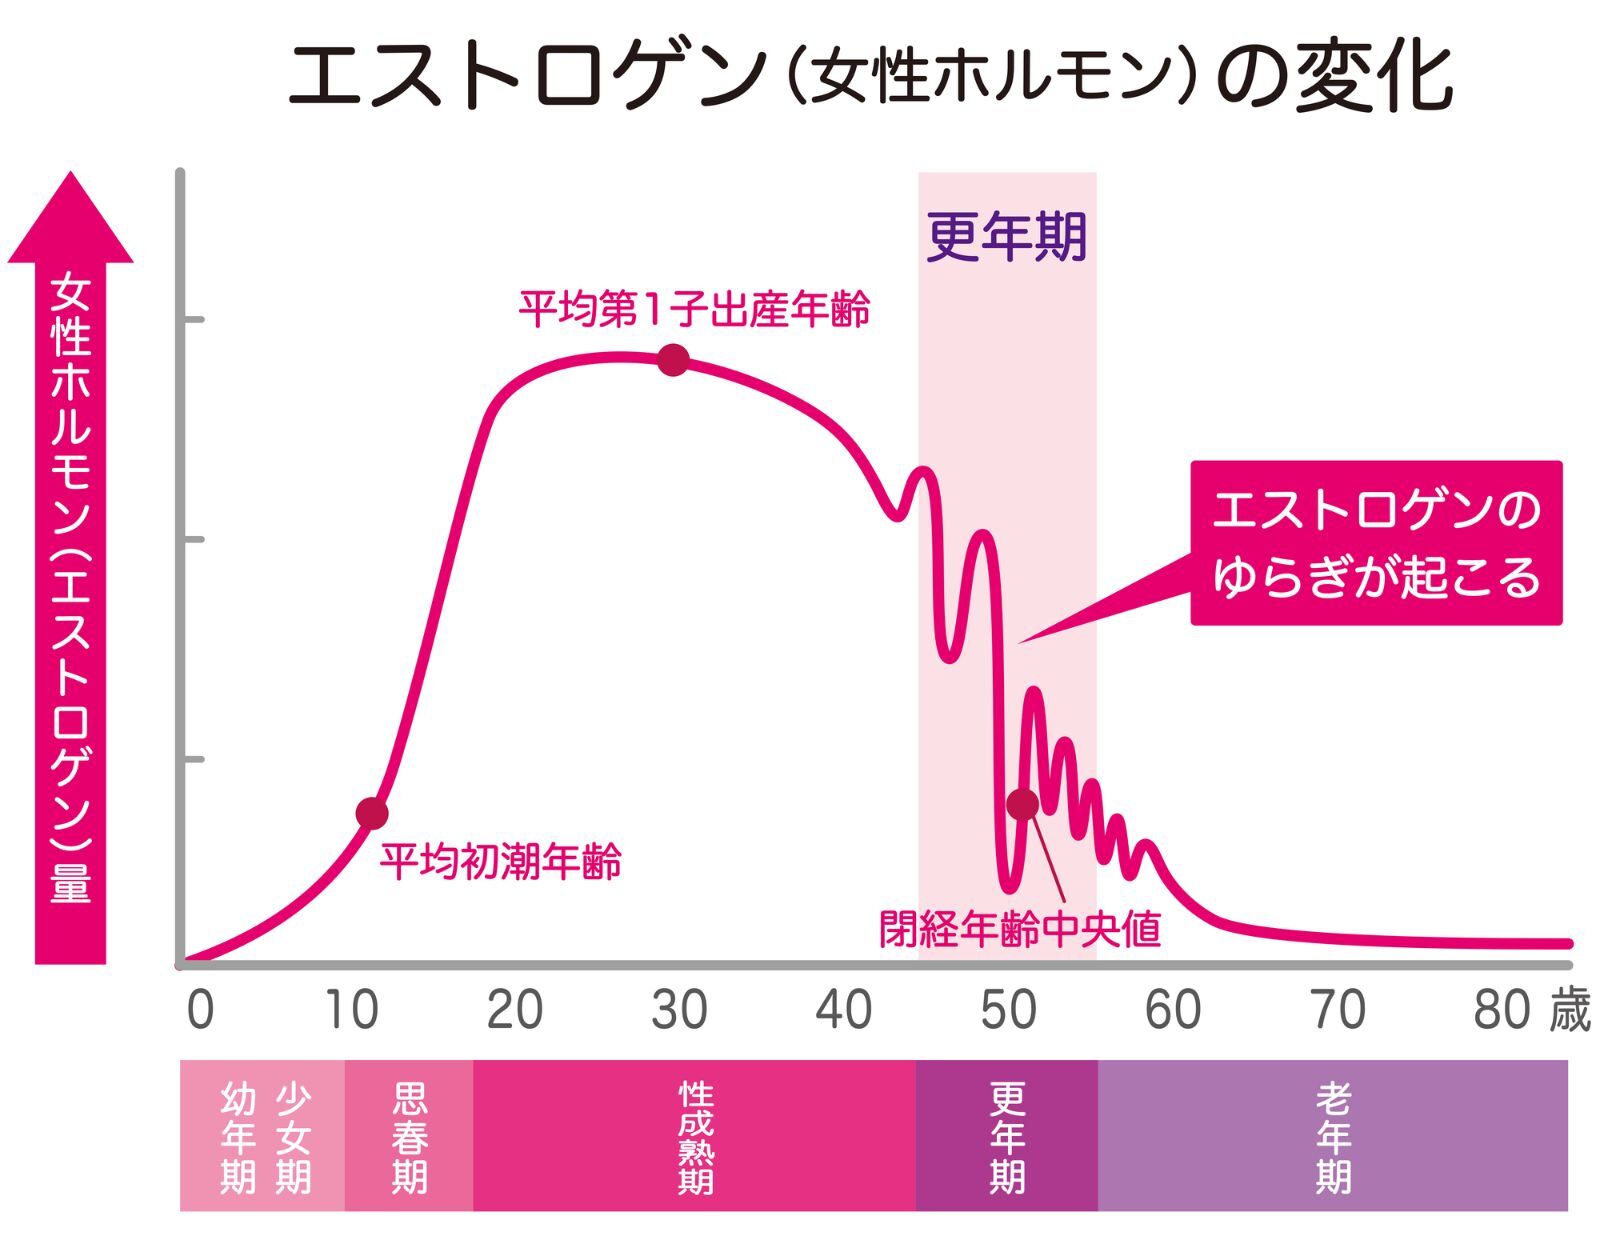

30代で体が急変するそうです

- 卵子の数と質が低下

- ホルモンバランスの変化

- 卵巣機能の低下

- 代謝や体重管理が難しくなる

30代になると

女性ホルモンが急変